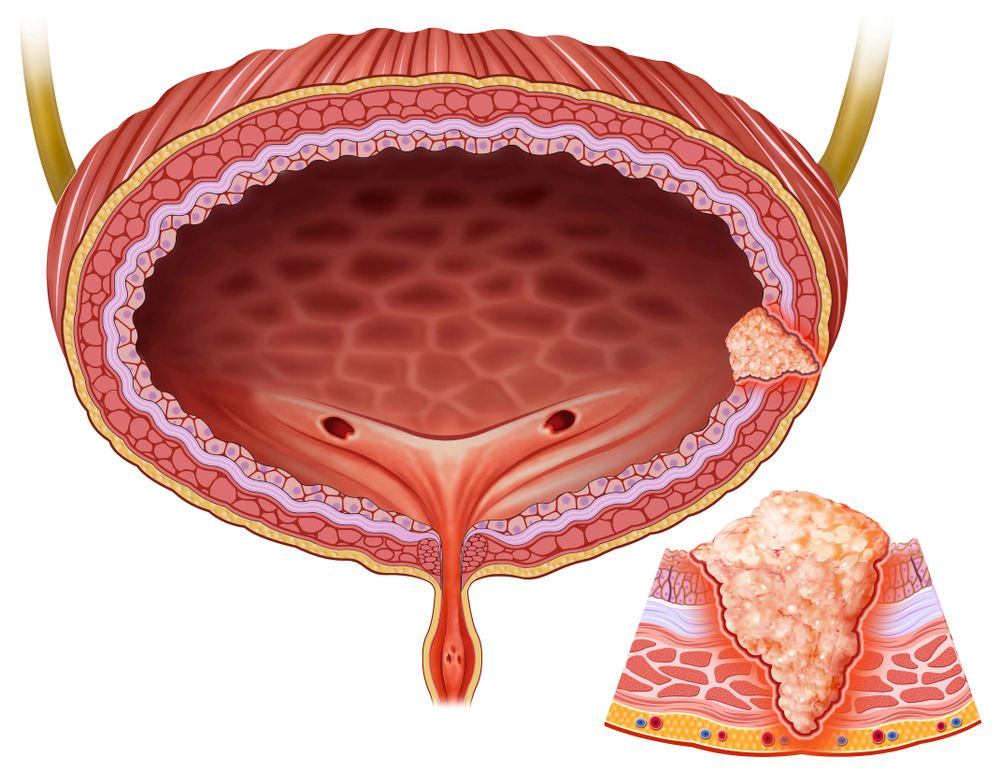

Mesane (idrar kesesi), böbreklerden süzülen idrarı depolayan, kas yapısında, esnek bir organdır. Mesane kanseri, çoğunlukla mesanenin içini kaplayan “ürotelyal” hücrelerde başlar. Bu hücreler, idrarla temas eden ilk bariyerdir ve idrardaki zararlı maddelerden en çok etkilenen yapıdır.

Hastalık, tümörün mesane duvarındaki yayılımına göre sınıflandırılır. Eğer kanser hücreleri sadece iç yüzeyde kalmışsa “yüzeysel” veya “kasa yayılmamış” mesane kanseri olarak adlandırılır. Ancak hücreler mesanenin kas tabakasına veya daha derin dokulara ilerlediyse, buna “invaziv” yani kasa yayılmış mesane kanseri denir. Tedavi planlaması tamamen bu ayrıma göre yapıldığı için, hastalığın evresini doğru belirlemek hayati önem taşır.